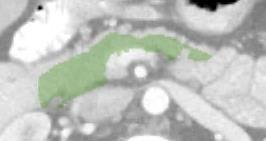

In this paper, we adopt 3D Convolutional Neural Networks to segment volumetric medical images. Although deep neural networks have been proven to be very effective on many 2D vision tasks, it is still challenging to apply them to 3D tasks due to the limited amount of annotated 3D data and limited computational resources. We propose a novel 3D-based coarse-to-fine framework to effectively and efficiently tackle these challenges. The proposed 3D-based framework outperforms the 2D counterpart to a large margin since it can leverage the rich spatial infor- mation along all three axes. We conduct experiments on two datasets which include healthy and pathological pancreases respectively, and achieve the current state-of-the-art in terms of Dice-S{\o}rensen Coefficient (DSC). On the NIH pancreas segmentation dataset, we outperform the previous best by an average of over 2%, and the worst case is improved by 7% to reach almost 70%, which indicates the reliability of our framework in clinical applications.